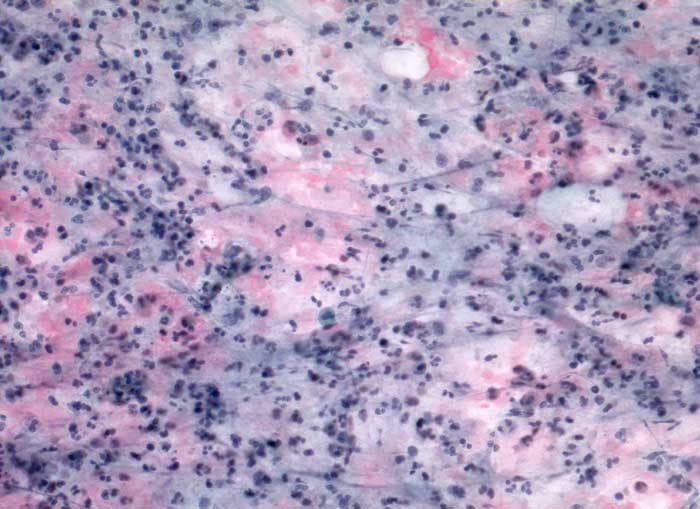

Akute Sialadenitis

Parotis

Akute bakterielle Sialadenitiden werden oft verursacht durch eine Gangobstruktion (z.B. Steine), können aber auch bei schlechter Mundhygiene oder bei Immunsupression vorkommen. Die Feinnadelpunktion kann durch eine Druckverminderung zu einer Schmerzreduktion führen. Das Punktat gleicht einem Abszess mit neutrophilen Granulozyten, Fibrin und Nekrosen. Gelegentlich sind Erreger nachweisbar. Zu einem späteren Zeitpunkt kommen Lymphozyten, Plasmazellen, Makrophagen, Granulationsgewebe und Epithelien mit regenerativen Veränderung/Atypien zur Darstellung.